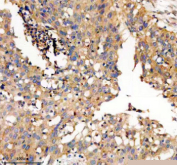

Immunohistochemical staining of TWSG1 using anti-TWSG1 antibody. TWSG1 was detected in a paraffin-embedded section of human bladder cancer tissue. Heat mediated antigen retrieval was performed in EDTA buffer (pH 8.0, epitope retrieval solution). The tissue section was blocked with 10% goat serum. The tissue section was then incubated with 2 ug/ml rabbit anti-TWSG1 antibody overnight at 4oC. Peroxidase Conjugated Goat Anti-rabbit IgG was used as secondary antibody and incubated for 30 minutes at 37oC. The tissue section was developed using an HRP secondary and DAB substrate.